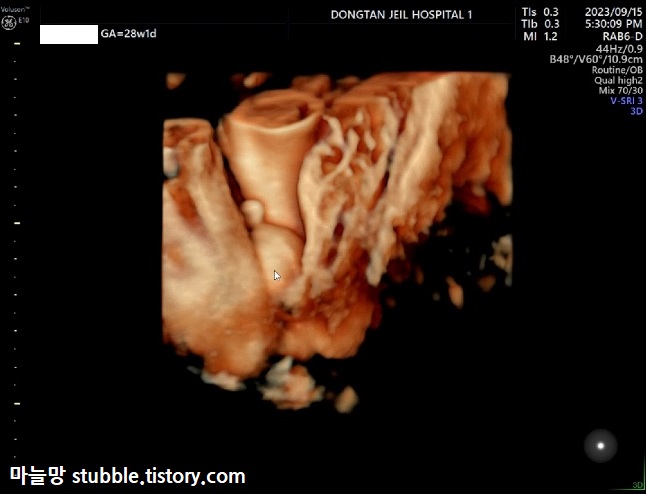

성별 사진입니다.

짐작하셨겠죠?